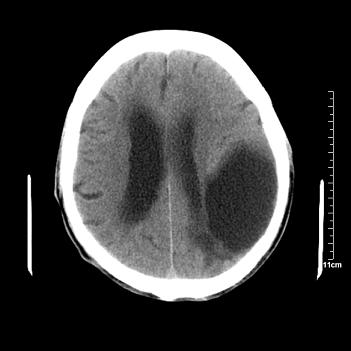

男性患者,72岁,近两天头晕来我院就诊。 因患者血压太高而未做增强,建议病人去市医院做mri检查。等得到mri随访结果再公布给大家。 测及左颞顶枕叶病灶ct值分别为5hu 30hu 729hu。

考虑左侧颞顶枕叶少突胶质细胞瘤。 今天随访患者手术病理结果 病理回报为胶质瘤2级 钙化

左侧颞顶枕叶大片状低密度影,呈均一水样密度,边界清楚,病灶边缘不规则片状钙化,左侧脑室后角扩大,中线结构未见移位,综合来看不像肿瘤,软化灶,钙化不好解释

左侧颞顶枕叶巨大囊性病灶,灶内见小片实性区且灶内及灶周围大量团块状钙化影,灶周水肿少.左侧室枕角内见环形钙化,可见较清晰前壁,钙化与室壁似有间隙.

囊变明显,钙化明显,部分实性组织,轻度占位,左侧脑室受压---考虑 少突胶质细胞瘤,畸胎瘤,寄生虫病

今天追踪患者家属手术病理结果 病理回报为胶质瘤2级并钙化

病理回报为胶质瘤2级并钙化